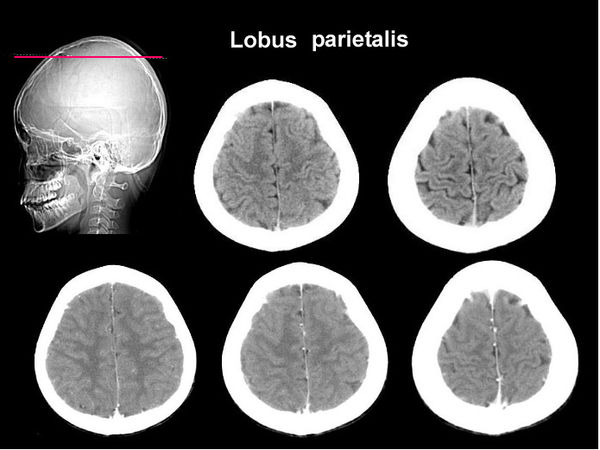

CT brain scans of a healthy subject fo comparison (not out of a Hamer book)

A modern scanner is used here, picture quality is far better.